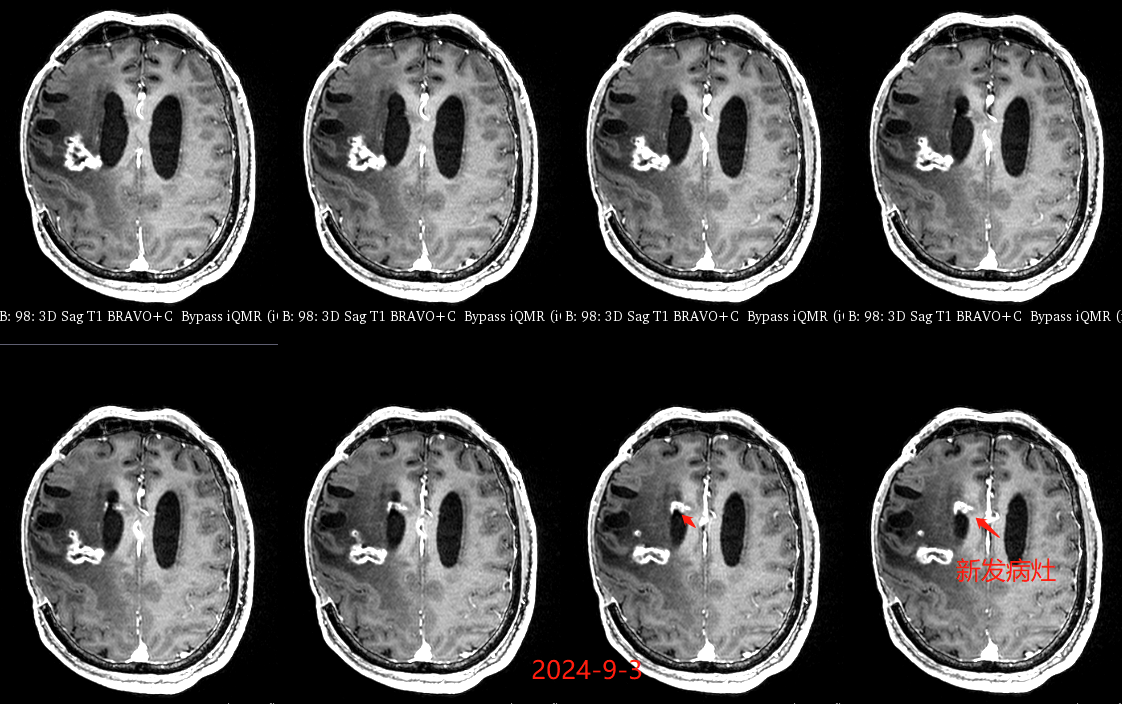

入院后于当地医院完善头颈部CTA检查未见明显血管发育异常,于2023-6-7行血肿钻孔引流术+脑室内颅内压监护探极置入术,引流一周后拔除引流管,期间未行尿激酶注射,患者反应情况逐渐好转,肌力未见明显改善。于出血后3周左右脑水肿基本消退后出院行康复治疗,治疗过程中患者肌力曾有所改善,左侧肢体肌力最好可达3级。术后3月左右患者一般状态逐渐变差,无发热,神志逐渐进展为昏睡状态,左侧肢体肌力1级,复查颅脑CT示水肿较前明显加重,颅脑MRI示右侧基底节区长T1长T2团块状病变,内有囊变,呈不均匀菜花样强化,考虑为高级别胶质瘤可能性大。遂行开颅病灶大部切除+去骨瓣减压术,术后病理提示高级别胶质瘤伴囊变,后续行同步放化疗STUPP方案,PTV:60Gy/30F/6周,替莫唑胺350mg化疗。患者右侧基底节区病灶相对稳定,2024-9-3复查颅脑MRI可见脑室内新发病灶。患者目前KPS 60分,神志清醒,精神差,反应迟钝,语言对答部分切题,右侧肢体自主活动,左侧肢体肌力2级。